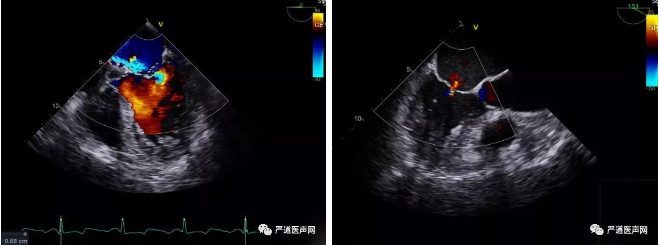

当得知上海长海医院正在进行MitralStitch®二尖瓣瓣膜修复系统的临床研究时,老人的家人找到陆方林主任,希望寻求一线希望。住院后心脏超声提示老人的二尖瓣后瓣脱垂,并已发展成重度关闭不全,瞬时反流量达35ml,左心也已扩大。经过全面的评估后,心脏团队和核心实验室认为该患者适合临床研究入组,可接受MitralStitch®系统手术治疗。完善术前准备和知情告知后,老人终于如愿入选临床研究。手术团队于患者肋间行3-4cm小切口,术中操作在单纯超声引导下进行,过程平稳顺利,从器械导入到完成人工腱索植入,仅耗时约10分钟,术后二尖瓣反流量由大量反流转为微量反流,瞬时反流量不超过2ml,瓣膜功能即刻恢复正常。老人术后第一天就回到了普通病房,第二天就可以下床活动了。这也是目前国内MitralStitch®二尖瓣瓣膜修复系统应用的年龄最大的病例。老人及家属在术后表达了深切的感激之情,表示MitralStitch®二尖瓣微创修复的“中国方案”为重症二尖瓣反流患者带来了新的生命曙光。

心超术前术后对比